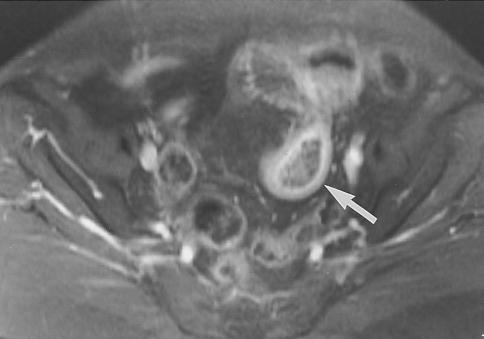

4. MRI

Nhạy hơn về những những thay đổi viêm ở vùng quanh túi thừa Meckel. Nếu có lạc chỗ niêm mạc tuyến dạ dày thì lớp này sẽ hiện rõ do bắt thuốc cản từ ngay lập tức ở thì mao mạch (Capillary phase) và thì mô kẽ (interstitial phase).

Hình 6: Hình T1W xóa mỡ sau tiêm thuốc cản từ, túi thừa Meckel có dạng hình giọt nước (mũi tên). Lớp trong bắt thuốc cản từ mạnh hơn lớp niêm mạc của đại tràng và hồi tràng, đó là lớp niêm mạc dạ dày lạc chỗ. (Diego R. Martin, Ersan Altun, Jorge Elias et al (2010). Gastrointestinal tract. In: Richard C. Semelka. Abdominal – pelvic MRI 3rd

edition.Wiley-Blackwell: P774)

Hình 7: Hình coronal T2W SSTSE (Single – short turbo spine-echo) cho thấy cấu trúc hình ống có đầu tận cùng nằm giữa dưới rốn, chứa đầydịch (mũi tên). Mỡ mạc treo có tín hiệu không đồng nhất do viêm. (Shilpa Hegde. Jonathan R. Dillman. Samir Gadepalli et al (2012). MR enterography of perforated acute Meckel diverticulitis. Springer Pediatr Radiol 42:259).